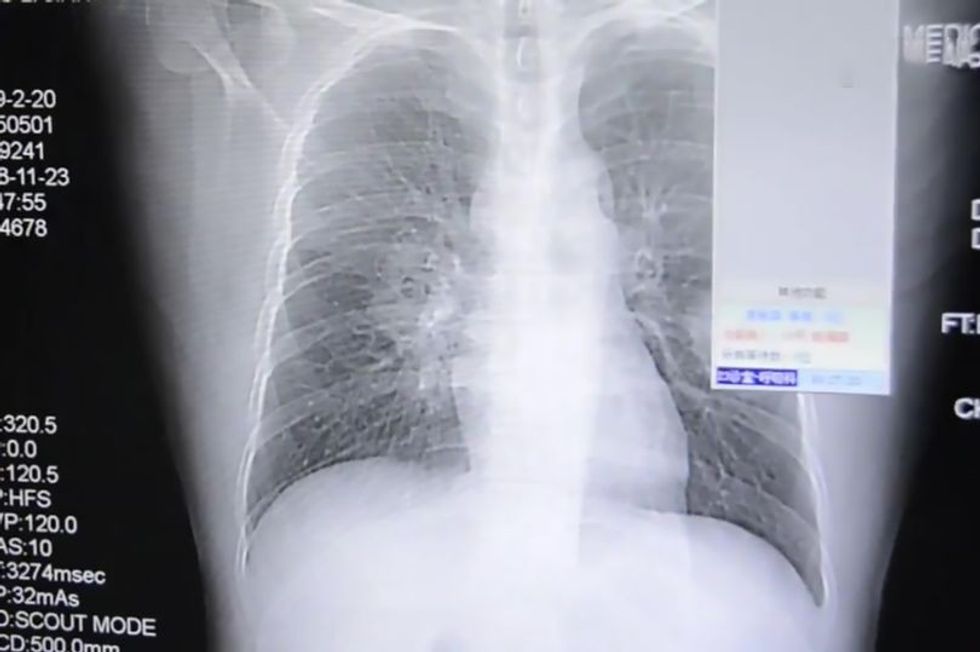

Atë e kishin pranuar në spital, pasi e dërgoi emergjenca me gjendje të rëndë shëndetësore, teksa fotografimi me rreze X, tregoi infeksionin në organet e frymëmarrjes.